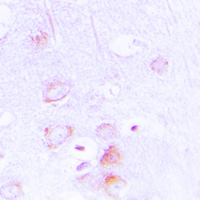

- Immunohistochemical analysis of EPB41L2 staining in human brain formalin fixed paraffin embedded tissue section. The section was pre-treated using heat mediated antigen retrieval with sodium citrate buffer (pH 6.0). The section was then incubated with the antibody at room temperature and detected using an HRP conjugated compact polymer system. DAB was used as the chromogen. The section was then counterstained with hematoxylin and mounted with DPX.